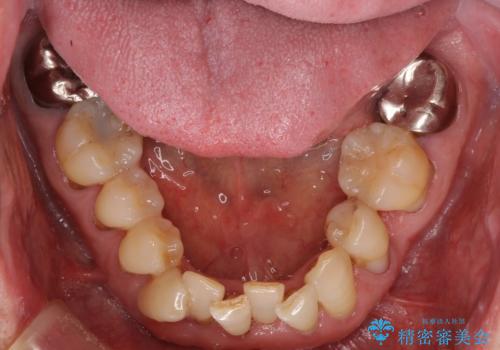

- 上の前歯が痛むとのことで来院された患者様です。

検査を行ったところ、前歯1本は周辺の骨が失われており、抜歯が必要でした。

上顎の奥歯は全体的に歯周ポケットが散見され出血が認められたため、歯周外科処置を行うこととしました。

また、前歯の部分矯正も希望されたため、歯周外科処置と平行して矯正治療を行うこととしました。